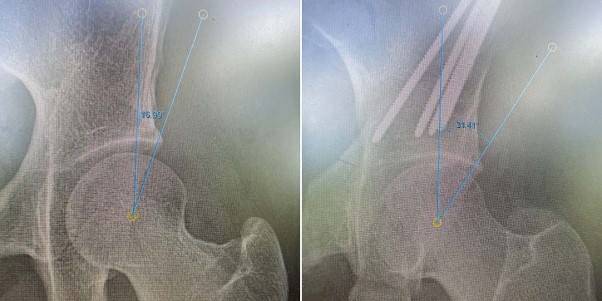

Preoperative and postoperative X-rays of a patient with persistent pain after prior hip arthroscopy who underwent combined revision hip arthroscopy and periacetabular osteotomy by Dr. Van De Velde and Dr. Christian.